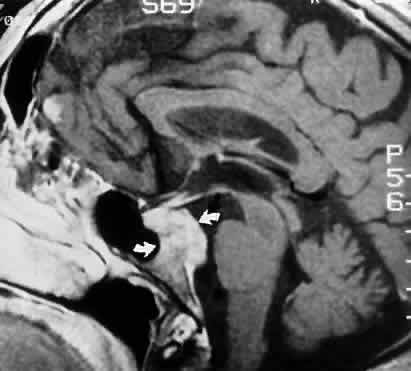

FASCICULAR LESIONS Deficits of the oculomotor fasciculus are usually identified by the accompanying brain stem signs. Oculomotor palsy with contralateral hemiplegia (Weber syndrome) indicates involvement of the corticospinal tracts. Contralateral ataxia and intention tremor (Benedikt syndrome) indicates involvement of the red nucleus (see Fig. 2). Nothnagel syndrome is an eponym given when signs of both Weber and Benedikt syndromes are present. Midbrain vascular accidents account for most fascicular defects. Ksiazek84 shed some light on the fascicular arrangement of the oculomotor nerve based on two patients with partial oculomotor paresis, each with pupillary mydriasis, significant inferior rectus paresis, and medial rectus paresis. Neuroimaging revealed a lesion in the fascicular portion of the nerve, thus indicating the proximity of these fibers in the fasciculus. Monocular elevator paresis (superior rectus and inferior oblique) in mass compression of the oculomotor fasciculus has also been reported.85 In this regard, Castro and associates86 proposed the mediolateral somatotopy of the oculomotor fascicular fibers within the mesencephalon with the inferior oblique and superior rectus muscles being most lateral, and the pupilloconstrictor fibers and inferior rectus being most medial. The levator palpebrae fascicles are in an intermediate location between the superior rectus and medial rectus fascicles. INTERPEDUNCULAR LESIONS Basal lesions, including the rare rostral basilar artery aneurysm, may encroach on the oculomotor nerves as they exit in the interpeduncular space. Such slow-growing aneurysms, either saccular or fusiform, may present as partial oculomotor palsies with or without involvement of pyramidal tracts, and without subarachnoid hemorrhage.87 Aneurysms of the posterior communicating artery, on the other hand, are probably the most common lesions causing acute spontaneous oculomotor palsies (Fig. 12). According to Hyland and Barnett,88 the oculomotor palsy that occurs with posterior communicating aneurysm is not necessarily due to mass effect per se, but rather is attributed to hemorrhage that suddenly enlarges the aneurysmal sac to which the oculomotor nerve is adherent, or to hemorrhage into the substance of the nerve itself. Most patients present, therefore, with an intensely painful, complete unilateral oculomotor palsy in association with other signs and symptoms of subarachnoid hemorrhage. Few patients with symptomatic posterior communicating aneurysms are found in office waiting rooms: they are usually obtunded or comatose in emergency rooms. Involvement of pupillary fibers is such a consistent finding in third nerve palsies due to bleeding aneurysms that most clinicians concur in this useful dictum: a pupil-sparing, but otherwise complete, third nerve palsy is very unlikely to be due to posterior communicating aneurysms. Careful pupil evaluation may disclose subtle abnormalities in “apparent pupil-sparing,” especially in cases of aberrant regeneration or with chronic cavernous sinus lesions. Generally, in patients at least 50 years of age or older, an acute, isolated, painful oculomotor palsy that spares the pupil is caused by intraneural ischemia; nevertheless, these patients must be carefully observed for further evolution. In our opinion, an acute complete oculomotor palsy with moderate to major mydriasis, even when diabetes is present, is an indication for cerebral arteriography. It should be emphasized that magnetic resonance angiography may not detect aneurysms smaller than 3 to 4 mm.89 The clinical management of patients with relative pupil-sparing third nerve palsies remains in debate. Observation alone arguably is appropriate management of such patients; however, since practically every conceivable combination of partial ophthalmoplegia and pupillary abnormality has been reported in aneurysmal compression of the third nerve, it is better to err on the side of caution and perform angiography more frequently. It is incumbent upon the physician to evaluate carefully the proportion of ophthalmoplegia and ptosis in relation to the degree of pupillary abnormality when deciding appropriate workup of these patients. Again, the increasing sensitivity of magnetic resonance angiography has not yet entirely replaced formal angiography. Certainly, neurosurgical intervention requires conventional cerebral arteriography before surgical treatment. Capó and colleagues90 pointed out that the interval from onset to maximal ophthalmoplegia does not differentiate between microvascular (3.3 days) and aneurysm (3 days), but that failure to recover within 4 to 8 weeks requires further evaluation. Other partial oculomotor palsies occur regularly with cavernous sinus masses and parasellar syndromes (see below), accompanied by variable pupillary findings. Furthermore, both acute and chronic lesions may produce incomplete palsy of the superior division (supplying levator palpebrae and superior rectus muscles) or of the inferior division (medial and inferior recti, inferior oblique and pupillomotor fibers). If pain or first trigeminal division numbness are absent, and if the pupil is uninvolved, such fractional oculomotor pareses are regularly misinterpreted as myasthenia or local orbital inflammations. Guy et al91 described five patients with isolated ptosis and elevator paresis in abduction, consistent with selective “superior division” involvement. They also discussed five previously reported cases with the following respective diagnoses: (1) intracavernous aneurysm (usually with associated Horner's syndrome) and basilar artery aneurysm; (2) diabetic ophthalmoplegia; (3) meningitis; (4) dural lymphoma; and (5) postsurgical manipulation of parasellar structures. In essence, there was little anatomic correlation with the physical separation into superior and inferior oculomotor trunks that occurs in the cavernous sinus. Moreover, two patients sustained superior division palsies during surgical manipulation of the subarachnoidal portion of the oculomotor nerve trunk. A number of cases of inferior rectus paresis, isolated or in combination with ipsilateral or contralateral superior rectus paresis, have been construed as focal lesions involving the rostral portion of the oculomotor nuclear complex.80–82 Oculomotor palsy following head trauma is not rare, but probably occurs less frequently than traumatic fourth nerve palsies. As a rule, such closed-head injury causes loss of consciousness and is accompanied by skull fracture, but this is not invariable. Injury to the ocular motor nerves in road accidents was studied by Heinze,92 who dissected the cadavers of 21 fatal cases. He found that the relationship of frontal or temporal fractures to neural damage was unpredictable. In fact, intact nerves were encountered adjacent to gross fracture sites. The oculomotor nerve was damaged at three locations: (1) avulsion of the rootlets at their ventral exit from the brain stem; (2) contusion necrosis of the most proximal portion of the nerve trunk; and (3) intraneural and perineural hemorrhage of the nerve trunks at the level of the superior orbital fissure. Of great interest are Heinze's findings of focal hemorrhages in extraocular muscles, usually associated with fractured orbital bones. Eyster et al93 reported three patients with large basicranial tumors, who presented with oculomotor palsies precipitated by mild blows to the head that were insufficient to cause fracture or loss of consciousness. The oculomotor nerves were encased and stretched by tumor, which apparently rendered these tethered nerves vulnerable when innocent head blows abruptly shifted the brain. The authors pointed out that such atypical presentations of intracranial tumors may further mimic aneurysms, since subarachnoid hemorrhage does occasionally occur with tumors. Neetens94 reported an additional three cases of oculomotor nerve palsies after minor trauma in the presence of basal intracranial tumors; the trochlear nerve was involved in all three cases, and in two cases the oculomotor nerve was partially affected. Walter et al95 reported two instances of minor head trauma resulting in complete third nerve palsies attributed to occult posterior communicating artery aneurysms. We have seen a 45-year-old school teacher who experienced an immediate right abducens palsy when playfully slapped on the back of the head; within weeks, other cranial nerve palsies announced the presence of diffuse meningeal spread of carcinoma. In the United States, basilar meningitis is rare, but was formerly encountered with tuberculosis and syphilis. When the third nerve is involved in such cases, progressive defects are the rule and other cranial nerve palsies are commonly found. Oculomotor palsy may especially occur with meningitides in infants, including instances of viral and bacterial (e.g., Streptococcus pneumoniae, Haemophilus influenzae) infections.96 Oculomotor nerve compression by the proximal segment of the posterior cerebral artery, or by the uncus against the petroclinoid ligament, can be seen with increasing cerebral edema or with an ipsilateral expanding supratentorial mass, and it is often heralded by unilateral pupillary dilation (Hutchinson pupil). Progression rapidly leads to complete ocular motor nerve palsy. Keane97 reviewed the ocular motor signs of tentorial herniation, which include anisocoria and parasympathetic pupillary abnormalities, unilateral or bilateral ptosis, internuclear ophthalmoplegia, vertical gaze paresis, and partial third nerve palsies. CAVERNOUS SINUS LESIONS The oculomotor nerve may be involved by inflammatory disease, tumor, aneurysm, arteriovenous fistula, or thrombosis at the level of the cavernous sinus. The third nerve is usually involved in combination with the fourth, sixth, and ophthalmictrigeminal nerves, and accompanying sympathetic paresis may minimize pupillary dilation. The syndrome of the cavernous sinus, therefore, includes multiple ocular motor nerve palsies and pain or numbness in the first trigeminal division. In practice, lesions involving primarily the superior orbital fissure produce signs and symptoms that, with the possible exception of proptosis, cannot be distinguished from those of the anterior cavernous sinus. In particular, dural carotid cavernous fistulas that drain primarily into the inferior petrosal sinus may cause third nerve pareses without significant orbital congestion.98 Third nerve palsies due to lesions in the cavernous sinus tend to be partial in that all muscles innervated by the oculomotor branches need not be involved. This is especially true of pupillomotor fibers, such that the pupil may be normal or minimally involved. This “pupil- sparing” is offhandedly attributed to the superimposition of sympathetic paresis (Horner syndrome), but appropriate pharmacologic tests rarely substantiate this explanation (see below, Parasellar Syndrome). More likely, slowly expanding masses (e.g., infraclinoid aneurysm, meningioma) functionally spare the pupilloconstrictor fibers in the intracavernous portion of the oculomotor nerve. In addition, the levator, superior, inferior, and medial recti may be involved in unequal degrees, but progressive paresis evolves. (Once again, myasthenia must be suspected in any nonpainful, pupil-sparing, nonproptotic ophthalmoplegia, with or without ptosis.) Cavernous sinus lesions are further discussed below. Primary neurinoma of the oculomotor nerve is a relatively rare lesion that should be considered in children or young adults with insidious third nerve palsy. These may occur in the cavernous or interpeduncular portion of the nerve (Fig. 13).99,100